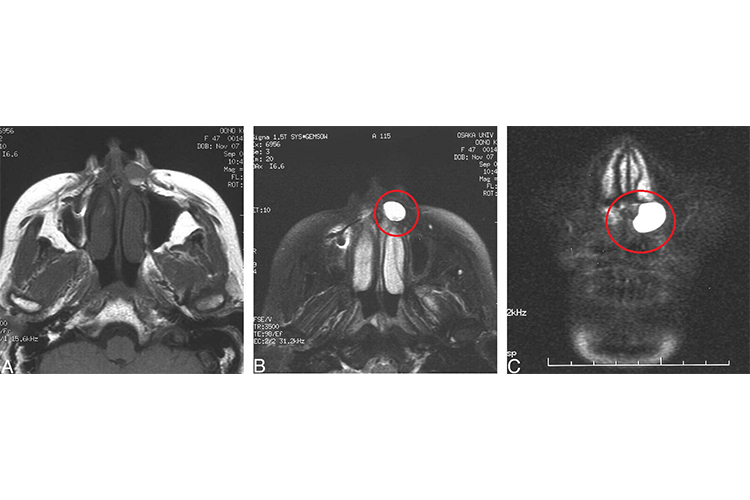

鼻前庭囊肿

囊肿发展缓慢,常单侧发病。早期囊肿小的时候无任何自觉症状。囊肿长大后,使一侧鼻前庭和鼻翼附着处隆起,伴鼻前庭部及上唇胀痛感,咀嚼时明显。囊肿较大阻塞鼻前庭时,可有同侧鼻塞。一些患者可有上颌部或额部反射性疼痛。若囊肿发生感染,可迅速增大,局部疼痛加重。